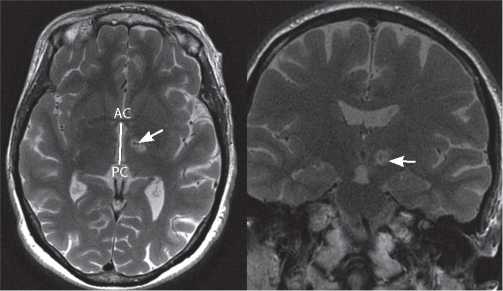

Во время процедуры МР-ФУЗ проводилось контрольное МРТ-исследование головного мозга в режиме T2 в аксиальной, сагиттальной и коронарной проекциях с толщиной среза 2 мм. Интраоперационная визуализация не выявила признаков кровоизлияния или нецелевого нагрева ни у одного из пациентов. После проведения лечения пациентам выполняли контрольное МРТ головного мозга через 2 и 24 ч, 30 дней: определялся незначительный отёк (1–3 мм) по краю и очаги некроза в местах воздействия (рис. 2).

Рис. 2. МРТ пациента через 30 дней после деструкции PTT справа методом МР-ФУЗ в аксиальной и коронарной проекции. Очаг деструкции указан стрелкой.

Fig. 2. Axial and coronal MR images in 30 days after right PTT MRgFUS destruction. The arrow indicates the destruction focus.